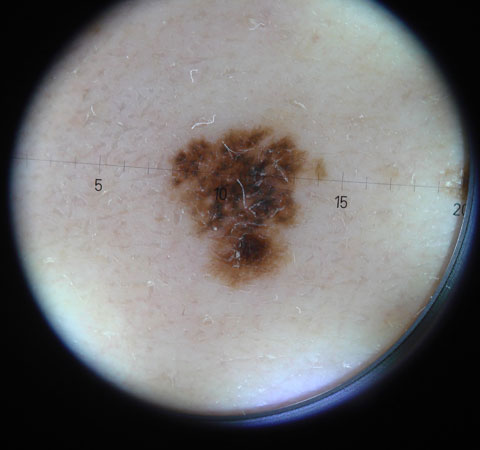

Σπίλοι - Μελάνωμα

Οι «εληές» ονομάζονται σπίλοι. Υπάρχουν πολλών μορφών και ειδών σπίλοι, στην πλειοψηφία τους καλοήθεις.

Υπάρχουν όμως και σπίλοι με ειδική εικόνα οι οποίοι μπορούν να μετατραπούν σε μία κακοηθέστατη μορφή, το μελάνωμα.

Ο εξειδικευμένος δερματολόγος μπορεί να υποδείξει ποιοι σπίλοι είναι καλοήθεις και ποιοί επικίνδυνοι για κακοήθη εξαλλαγή.

Σημαντική βοήθεια προσφέρει η χαρτογράφηση των σπίλων, δηλαδή η ηλεκτρονική καταγραφή και παρακολούθηση των σπίλων.